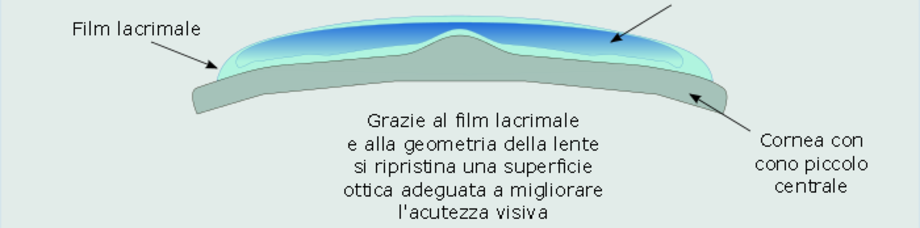

In verde è evidenziato il film lacrimale che riempie lo spazio tra cornea e lente a contatto. La superficie posteriore della lente viene costruita per adattarsi al cono, mentre l'uniformità della superficie anteriore ripristina un'adeguata ottica del sistema film lacrimale-cornea-lente a contatto che garantisce la miglior acutezza visiva.